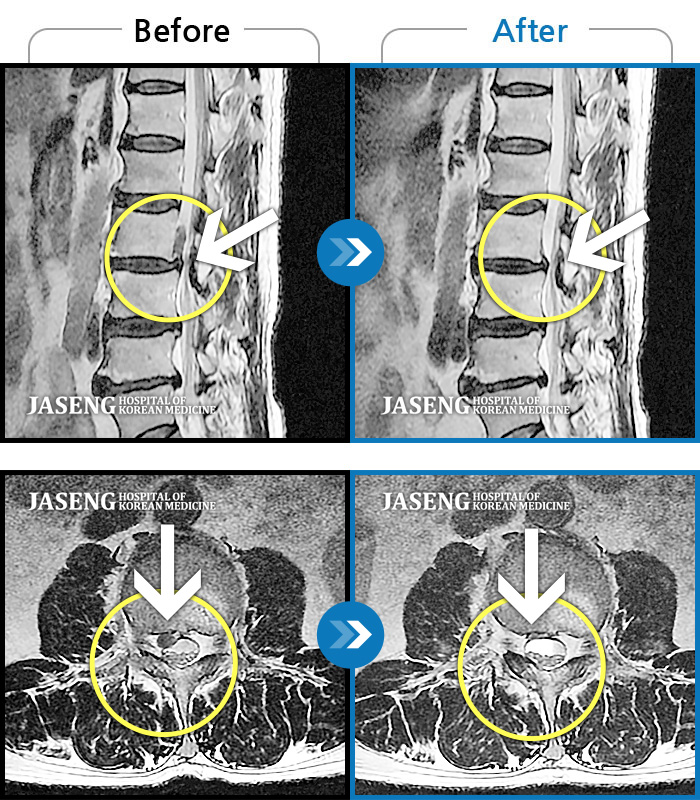

일산 · 배영현 원장

처음 내원 시 허리, 엉덩이가 많이 아프고, 좌측 다리에 힘이 빠지며 감각이 둔하여 정상적인 보행이 힘든 상태셨습니다.

촬영시기

2022.05.24 ~ 2023.05.13

2023.06.01